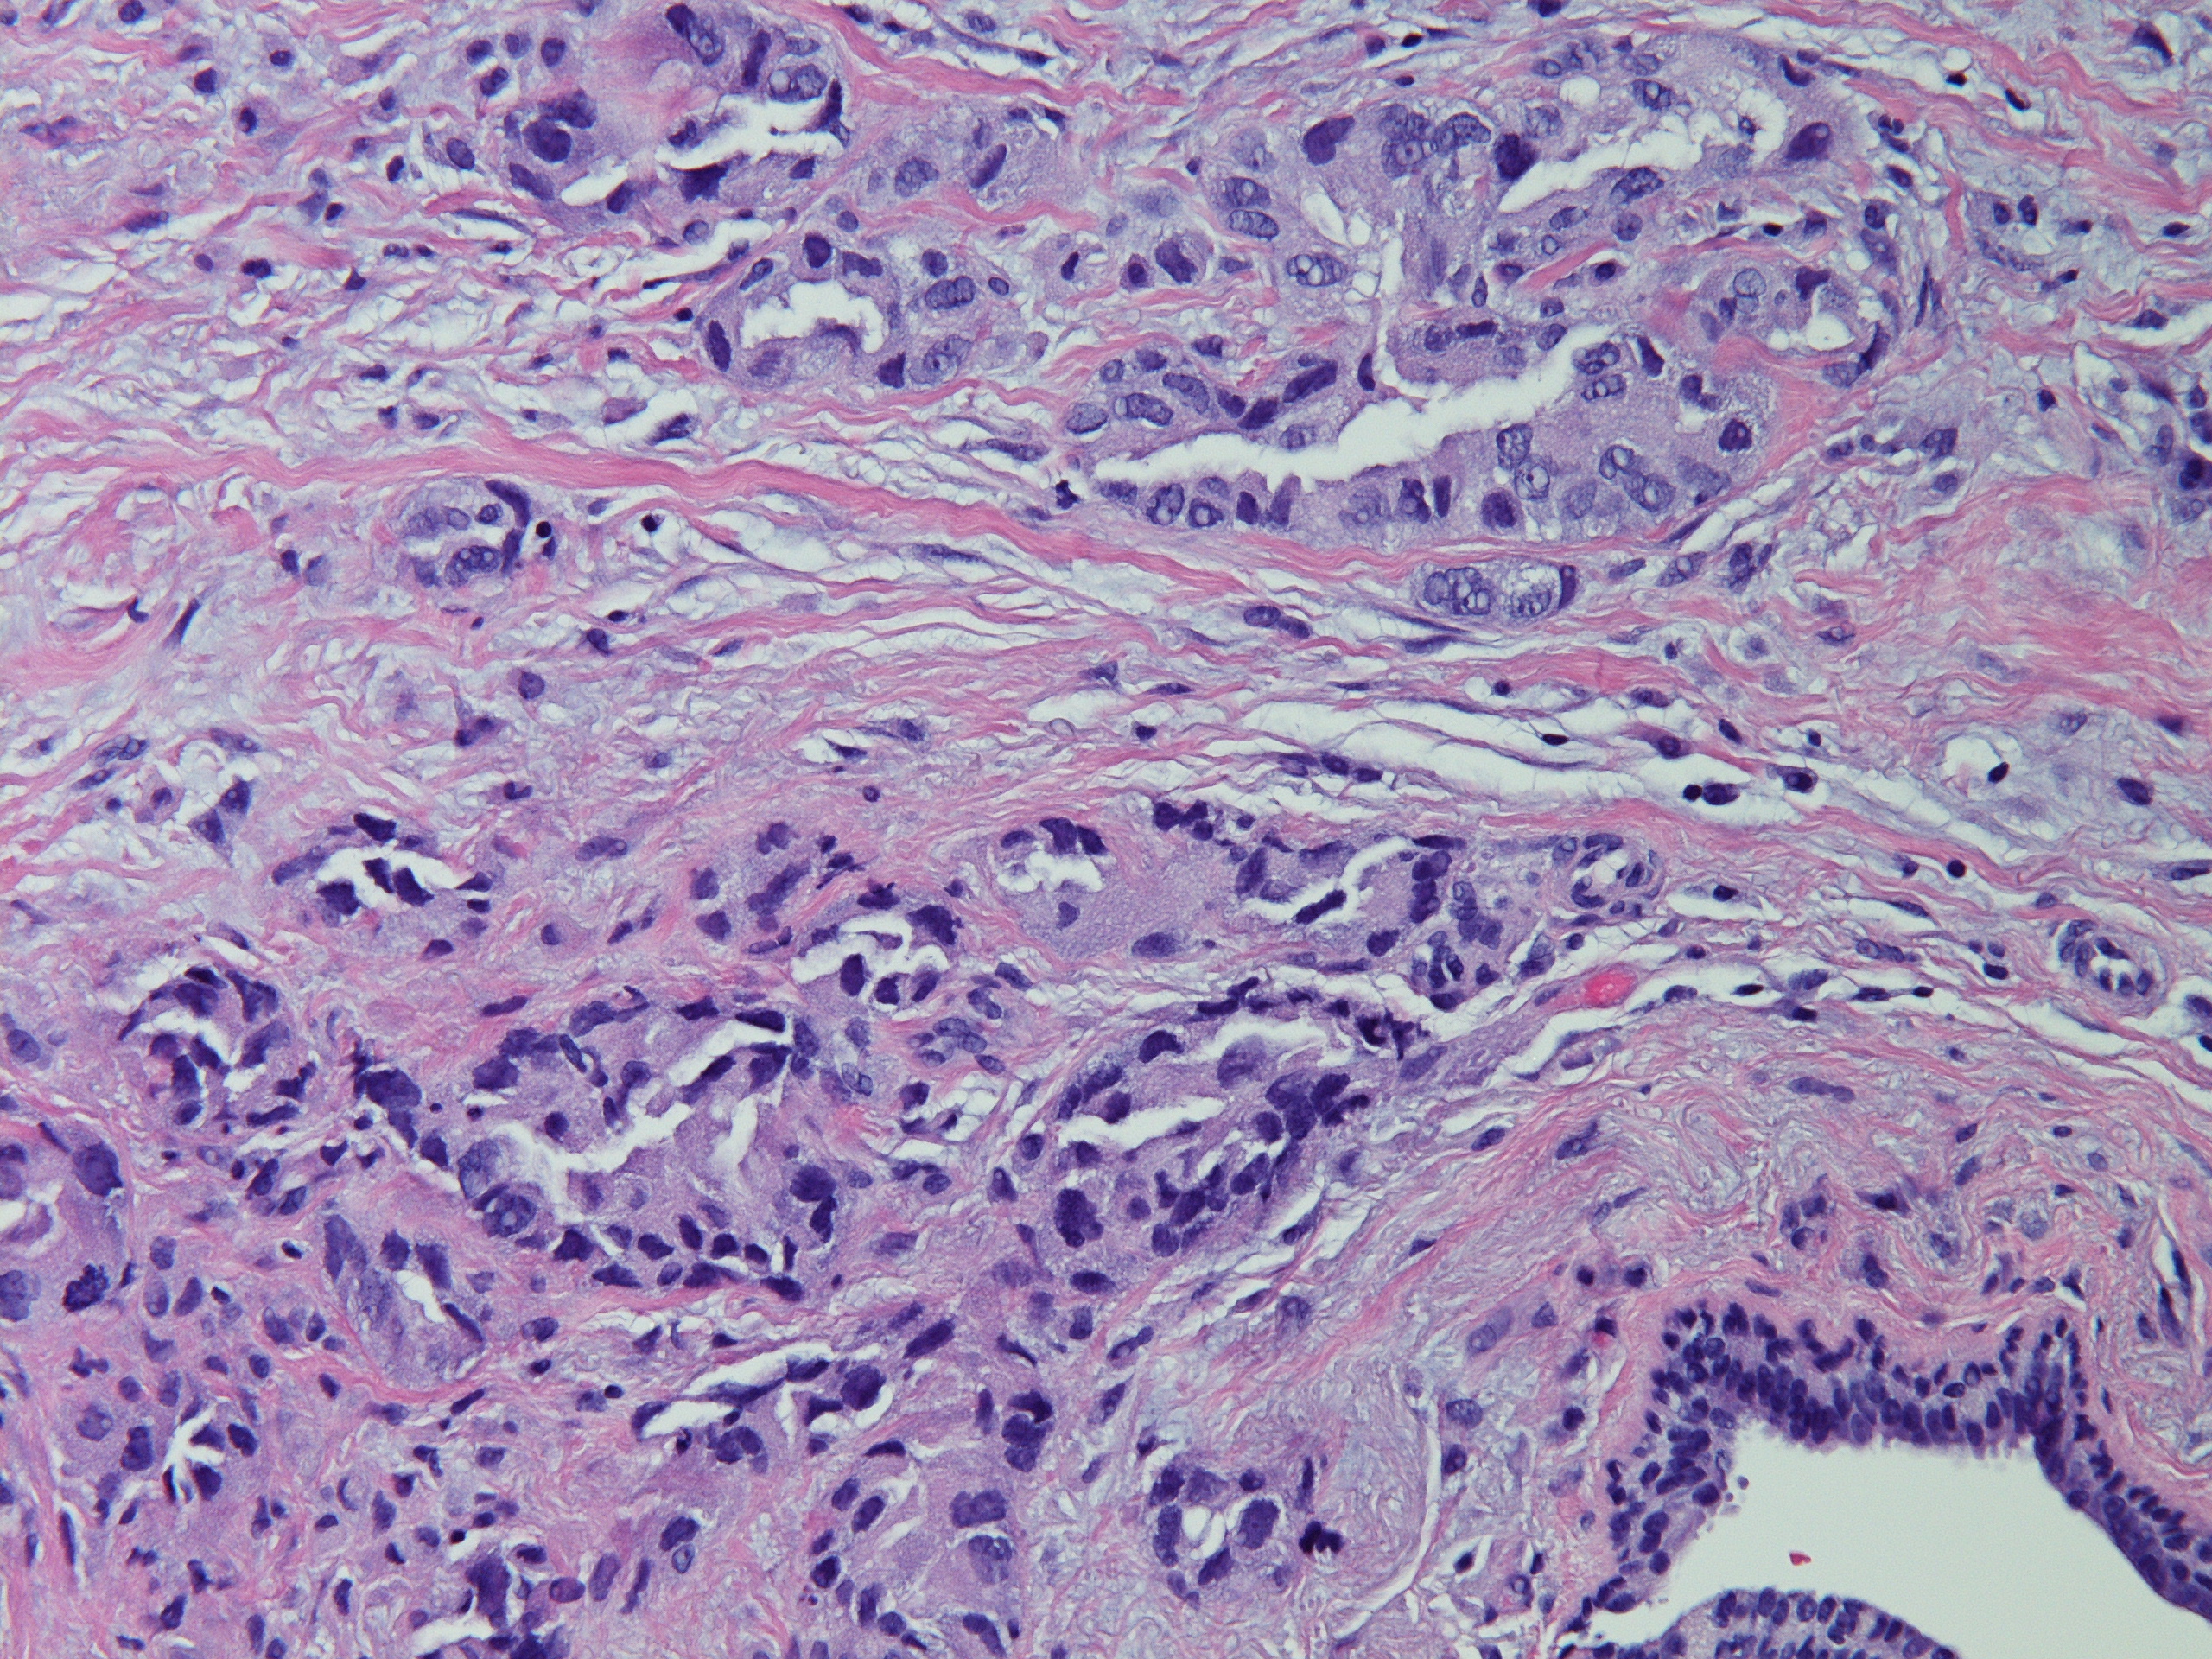

分享赵老师的一个病例:女,70岁,发现左侧乳腺肿块,2.5cm,行穿刺活检。无其他病史。

INVASIVE ADENOCARCINOMA, NUCLEAR GRADE 3.COMMENT:Multiple immunostains were ordered to determine it is a primary or metastatic tumor.

AddendumImmunostains were performed on the block. The tumor cells are positive for CK7, TTF-1, focally and weakly positive for ER, negative for PR and GATA-3, GCDFP, mammaglobin. The immunostain results support this is a metastatic carcinoma from pulmonary primary. This patient reportedly has metastatic adenocarcinoma of lung origin.AddendumNapsin A is positive, supporting a lung primary.

此例最后考虑是来自肺的转移性腺癌